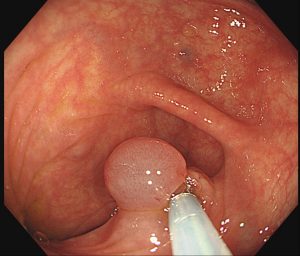

日本人の死因の多くを占めている大腸癌の早期発見のために、拡大内視鏡を用いた診断と患者様の検査の恐怖を和らげるよう努めております。 もし、ポリープが見つかった場合は希望があれば当日切除も可能です。その場合は、安全のため一泊入院していただきます。内視鏡的粘膜切除術:EMR 内視鏡的粘膜下層切開剥離術:ESD

内視鏡的粘膜切除術:EMR は、隆起していない病変、平坦な形の早期がん等に対して、粘膜下層に薬剤を注入することで病変部を盛り上げてからスネア(リング状の金属ワイヤー)で切除する方法です。

病変の大きさがスネアの大きさ程度(約2cm)であれば1回で切除することが可能です。